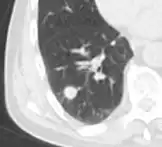

Low attenuating nodule (in this case a fat containing hamartoma).[9]

Low attenuating nodule (in this case a fat containing hamartoma).[9] Cavitation with relatively thick wall, in this case aspergilloma).[9]